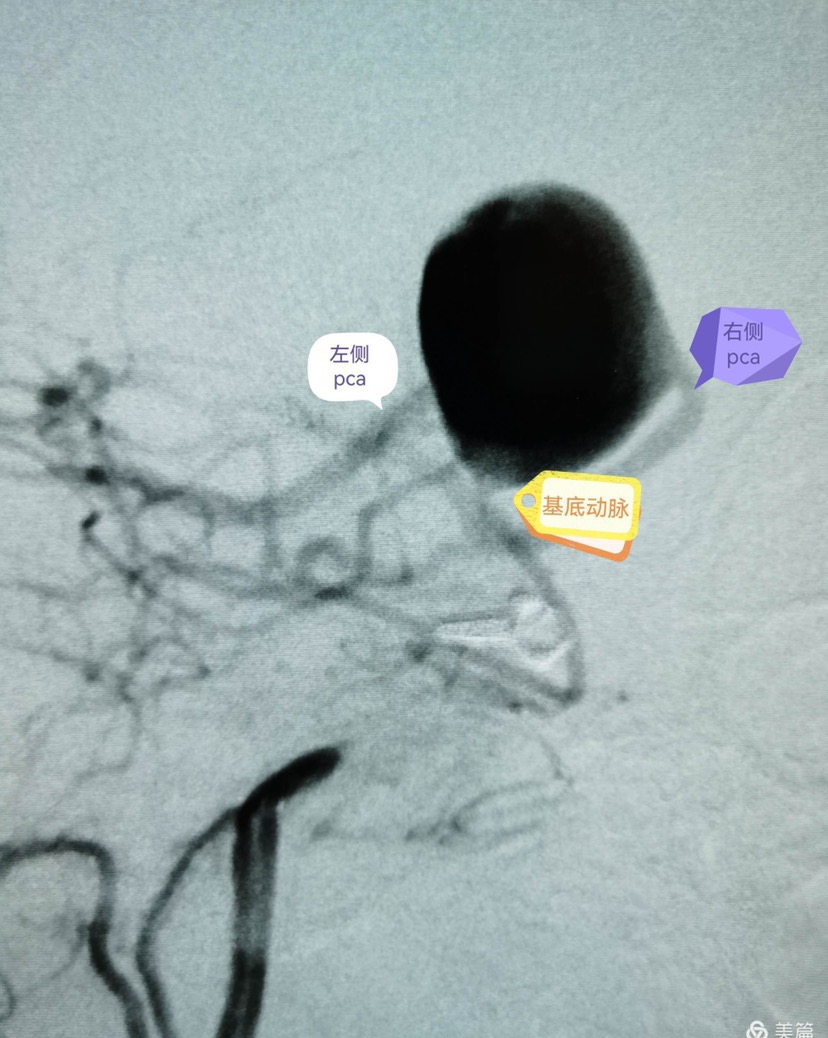

术后即刻造影显示瘤体中上部已完全不显影,仅下部可见造影剂,基底动脉各分支显影良好。

CTA及DSA显示:颈内动脉床突上段巨大动脉瘤(最大径25.6mm);基底动脉尖大动脉瘤(最大径20.3mm),瘤颈宽11mm,累及双侧大脑后动脉、小脑上动脉,右侧大脑后动脉自瘤体侧后方发出。